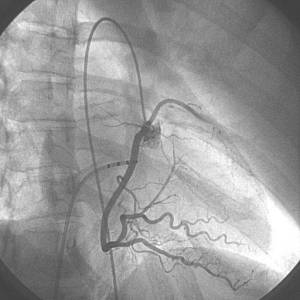

Διαγνωστικός καθετηριασμός (επιβεβαίωση της διάγνωσης)